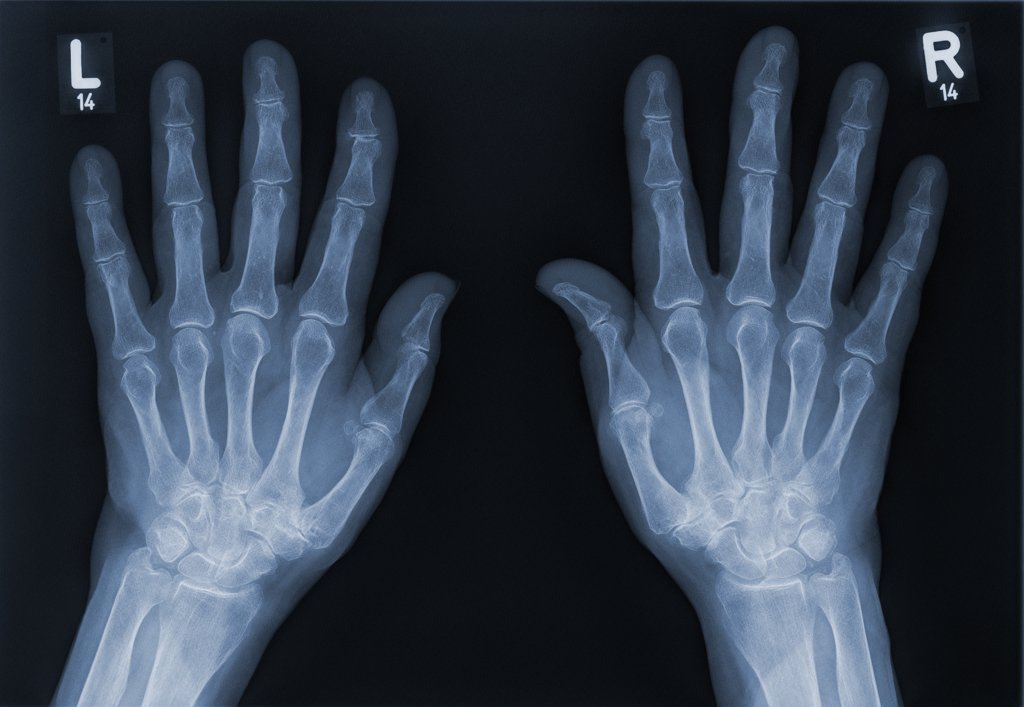

As doctors saw that that his health was declining, they broke the devastating news that they had to amputate JC''s legs below his knees and parts of all 10 of his fingers. He also needed a pacemaker for 13 days to treat his cardiac dysfunction.